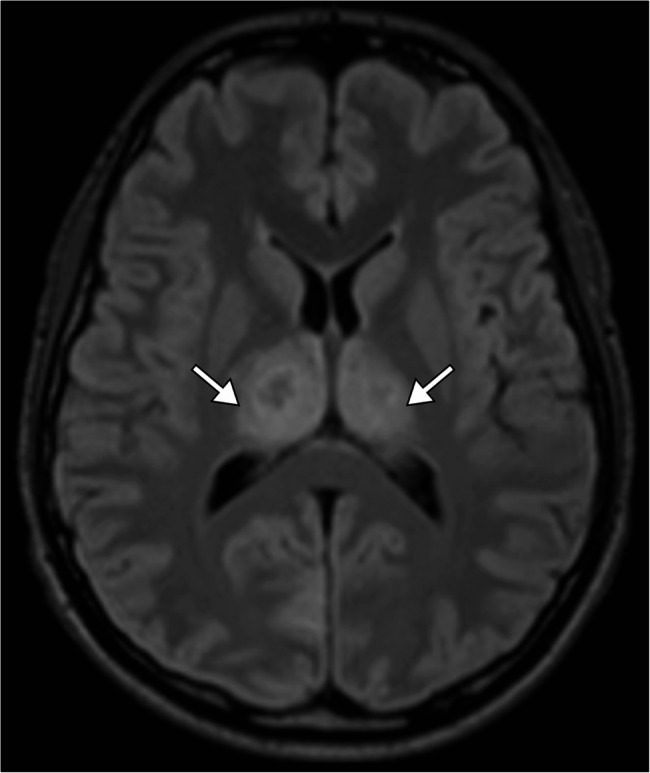

Case presentation: A 19-year-old previously healthy male presented with a two-day history of fever, headache, altered mental status, and seizures. On admission, he was febrile, with impaired consciousness. Initial investigations showed leukocytosis, elevated C-reactive protein, and cerebrospinal fluid analysis indicative of inflammation without bacterial or fungal pathogens. Brain MRI revealed bilateral symmetrical lesions in the thalami, putamen, and brainstem, consistent with acute necrotizing encephalopathy. Polymerase chain reaction testing of cerebrospinal fluid and nasopharyngeal swabs confirmed adenovirus as the causative agent. The patient was managed with seizure control, corticosteroids for cerebral edema, and supportive care, including mechanical ventilation and physiotherapy. Follow-up imaging demonstrated regression of thalamic and pontine lesions. The patient showed partial neurological recovery but required transfer to a long-term care facility for rehabilitation, with persistent functional disability.